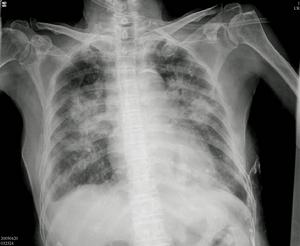

肺栓塞和肺梗死2、呼吸和心律增快、肺部羅音、肺動脈瓣第二心音亢進。胸片呈現肺部斑片狀或楔狀陰影,盤狀肺不張一側膈肌抬高,肺動脈增粗和局限性肺紋理減少。